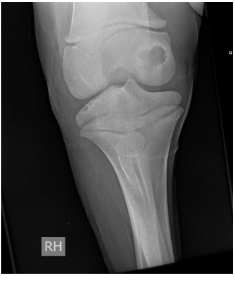

Fractuur van welke structuur?

Fractuur van de laterale condyl van de humerus